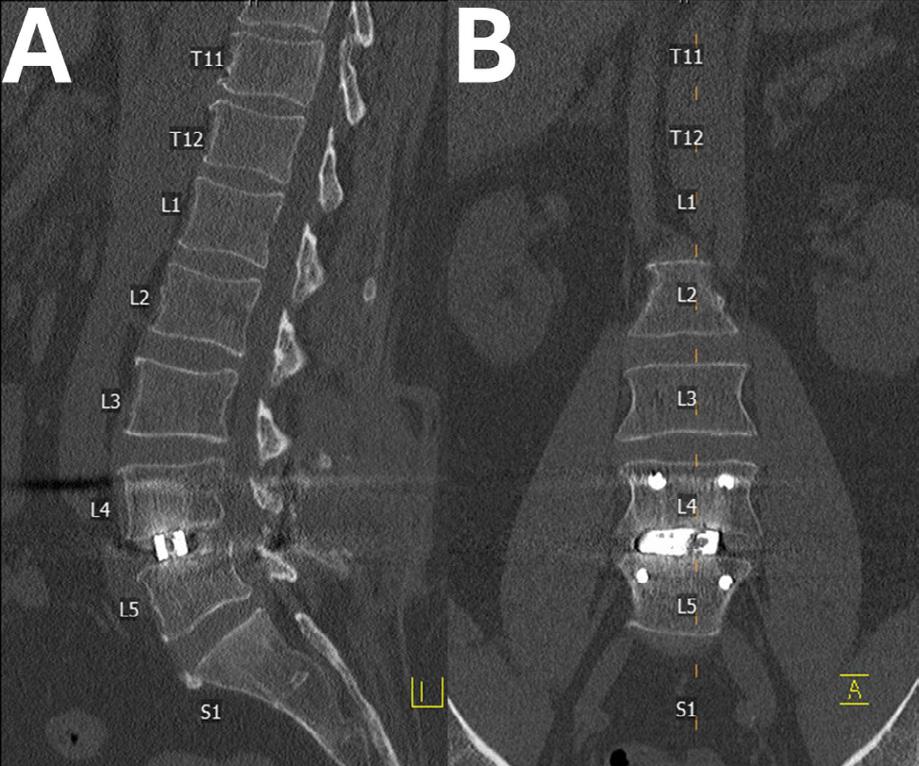

1. A 49-year-old man who had a prior L4-5 microdiscectomy by another provider had L4-5 spondylosis and recurrent disc herniation causing severe central and foraminal stenosis as seen on magnetic resonance images (B and C). Standing scoliosis radiograph (A) demonstrates collapse of the L4-5 disc space with loss of segmental lordosis.

the personalized fit of PSICs can streamline the surgical process. Fewer trials of implant sizes and decreased surgical remodeling of anatomy lead to less time in the operating room and fewer instruments being used and needing sterilization.1 A patient case is highlighted in Figures 1, 2 , and 3

Figure 3. Postoperative sagittal (A) and coronal (B) computed tomography images confirm satisfactory cage placement consistent with preoperative planning.